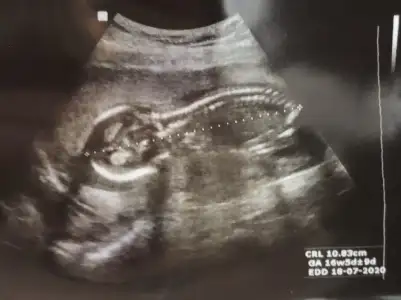

Bugün doktora gittik ama yüzüstü yatıyordu bir şey göremedik :))) siz keseye bakıp erkek, 12. Haftaya bakarak kız demiştiniz. Şimdi 17. Haftadayız:) ben erkek hissediyorum dedim doktor bence tam tersi sanki dedi 😁 sizce ne olabilir Ikra meyra Ikra meyra

12 de Kız tahmin etmiştim hale kız diyorum